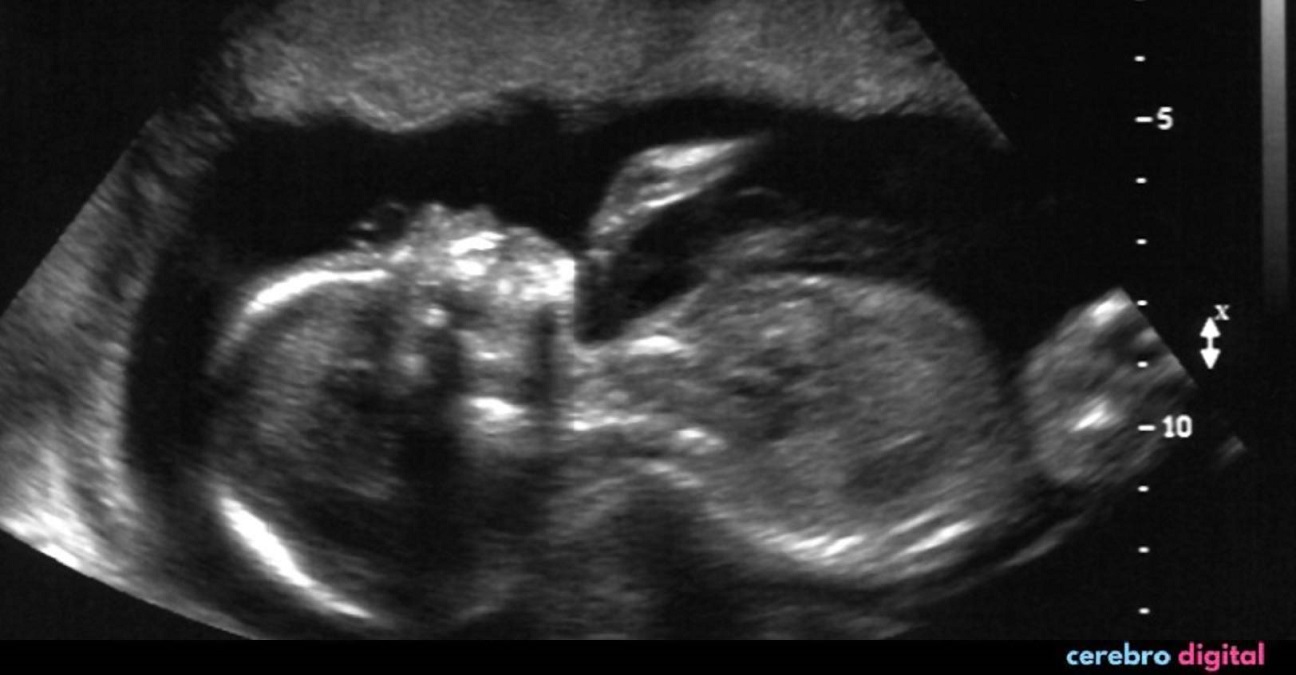

Hatcher, masajista y madre de tres hijos, ha documentado su viaje en su cuenta de Instagram «doubleuhatchlings» y, durante una ecografía realizada a las ocho semanas, descubrió que esperaba gemelos, cada uno de ellos en un útero distinto.